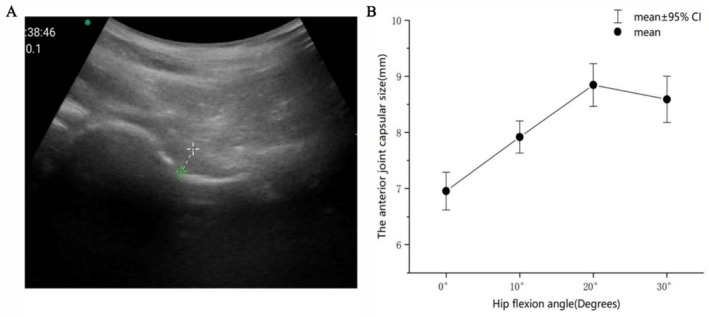

Methods: A single-center, prospective, randomized Williams crossover trial was conducted from March 2023 to June 2023 involving 30 patients with hip pain. Each patient underwent three hip joint punctures within 3 weeks, all conducted using anatomical landmark-guided blind puncture. The punctures were administered in different sequences of anterior, anterolateral, and lateral approaches, with one-week intervals between punctures. Thirty patients were randomly assigned to six groups (n = 5), following different sequences of the three approaches. The primary outcomes were the success rate and accuracy, and the secondary outcomes were post-puncture pain assessed using the Visual Analogue Scale (VAS), procedure time, puncture depth, and complications.

Results: The anterolateral approach achieved a higher success rate (96.7%) compared to the anterior (86.7%) and lateral (83.3%) approaches; although statistical significance was not reached (p = 0.328). Besides, it significantly shortened procedure duration (72.87 s, SD 9.66) compared to anterior (87.20 s, SD 20.57) and lateral (92.80 s, SD 39.02) approaches (p = 0.006). The puncture path length was shorter with the anterolateral approach (57.77 mm, SD 1.295) than with the lateral approach (63.33 mm, SD 1.295) (p = 0.004). The anterolateral approach achieved lower VAS pain scores (1.77, SD 0.94) compared to the lateral approach (2.90, SD 2.17). During the anterior approach injection, one patient experienced numbness in the lateral thigh of the surgical side.